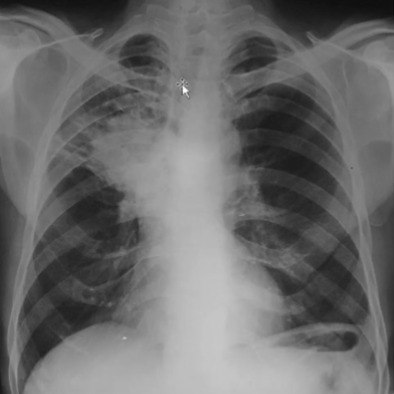

Rx toracică, incidență P-A

DESCRIERE:

pe tot teritoriul pulmonar, bilateral → opacități nodulare multiple de dimensiuni variabile, intensitate medie-mare, omogene, cu contur imprecis delim

confluente

distribuție anarhică

DX: bronhopneumonie

DD:

miliara TBC

MTS pulm hematogene